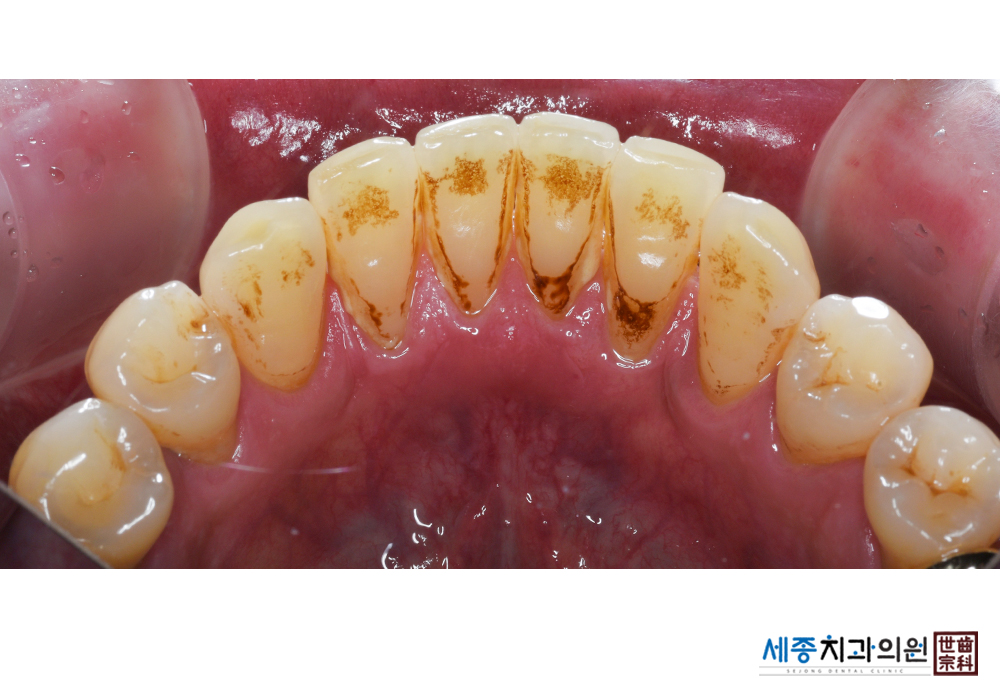

[스케일링] 치주질환 예방 스케일링 치료

치료전 : 2019-03-08

가글마취&저주파 스켈러를 사용한 스케일링